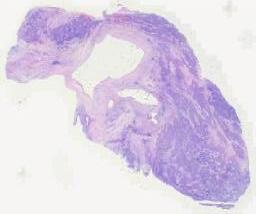

临床资料: 患者女,40岁,主诉:腹部包块5天。病史:患者5天前无意间发现腹部包块,伴轻度腹胀,行腹部超声提示肝囊肿,为行肝囊肿治疗入院。既往史:平素身体健康,否认高血压史、糖尿病史、冠心病史、输血史、手术外伤史、否认肝炎、结核等传染病史。否认药物、食物过敏史。实验室检测:肿瘤四项血清中甲胎蛋白、癌胚抗原、CA125、CA19-9含量均在正常范围。核磁及CT考虑感染性病变可能性大。